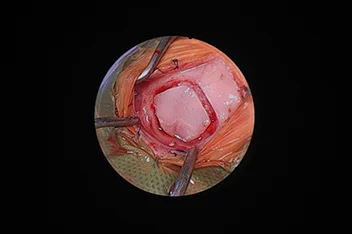

부울경 최초 ‘양방향 척추내시경’ 도입

정밀하고 덜 아픈 척추 수술의 새로운 패러다임

양방향 척추 내시경 BESS, Biportal Endoscopic Spine Surgery

기존의 단일 포털 내시경(uniportal endoscopy)의 한계를 극복한

정밀한 양손 작업이 가능한 최소침습 기술입니다.

리본동물의료센터 2025년 1월부터 부울경 최초로 양방향 척추 내시경을 도입해왔으며, 영남권 최다 임상 case를 축적하고 있습니다.

양방형 척추 내시경 수술의 핵심 장점

• 정밀한 수술 조작

• 근육 인대 손상 최소화

• 절개 최소화

• 빠른 회복과 낮은 통증

• 고배율 직시 시야 확보